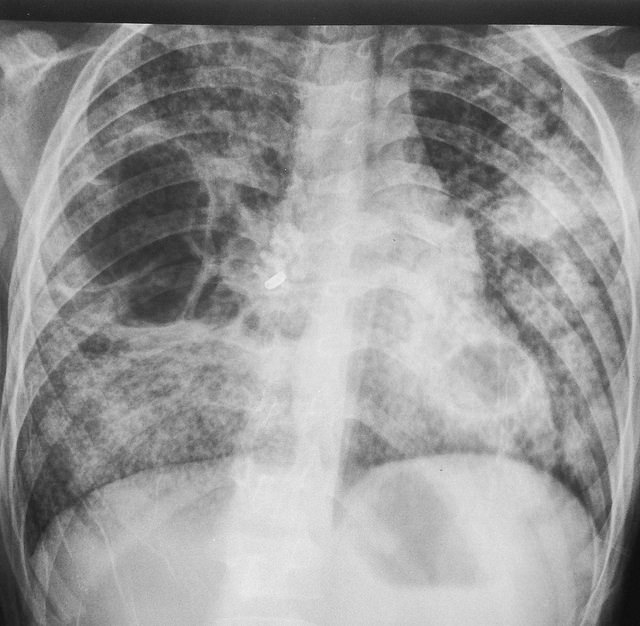

Lang niet iedereen die geïnfecteerd wordt met tbc wordt ziek. De bacteriën kunnen lang in een soort slaapstand blijven en bij een lage weerstand toeslaan. Áls je ziek wordt, dan wordt je ook echt goed ziek. De meest voorkomende vorm is longtuberculose, waarbij er gezwellen (tuberkels) met een soort witte pus in je longen ontstaan. Een belangrijk symptoom is hoesten. Daarnaast kan je last hebben van nachtzweten, vermageren en koorts. De gezwellen kunnen ook in andere organen in je lichaam ontstaan, waardoor deze aangetast worden.